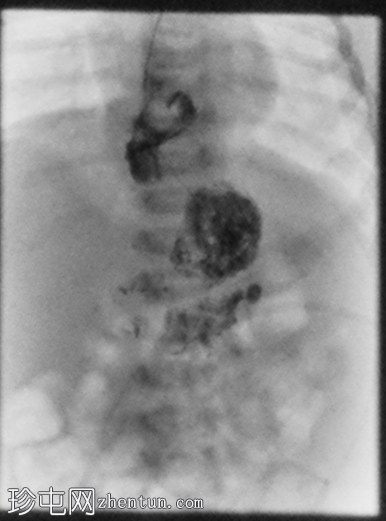

4.png

侧位(右侧卧位)

延迟1小时拍摄的X线片显示食管裂孔疝和胃部仍有造影剂残留,造影剂远端扩散受限,很可能是由于造影剂用量较少所致。充满气体的肠袢外观正常,乙状结肠内可见气体,直肠内未见气体。